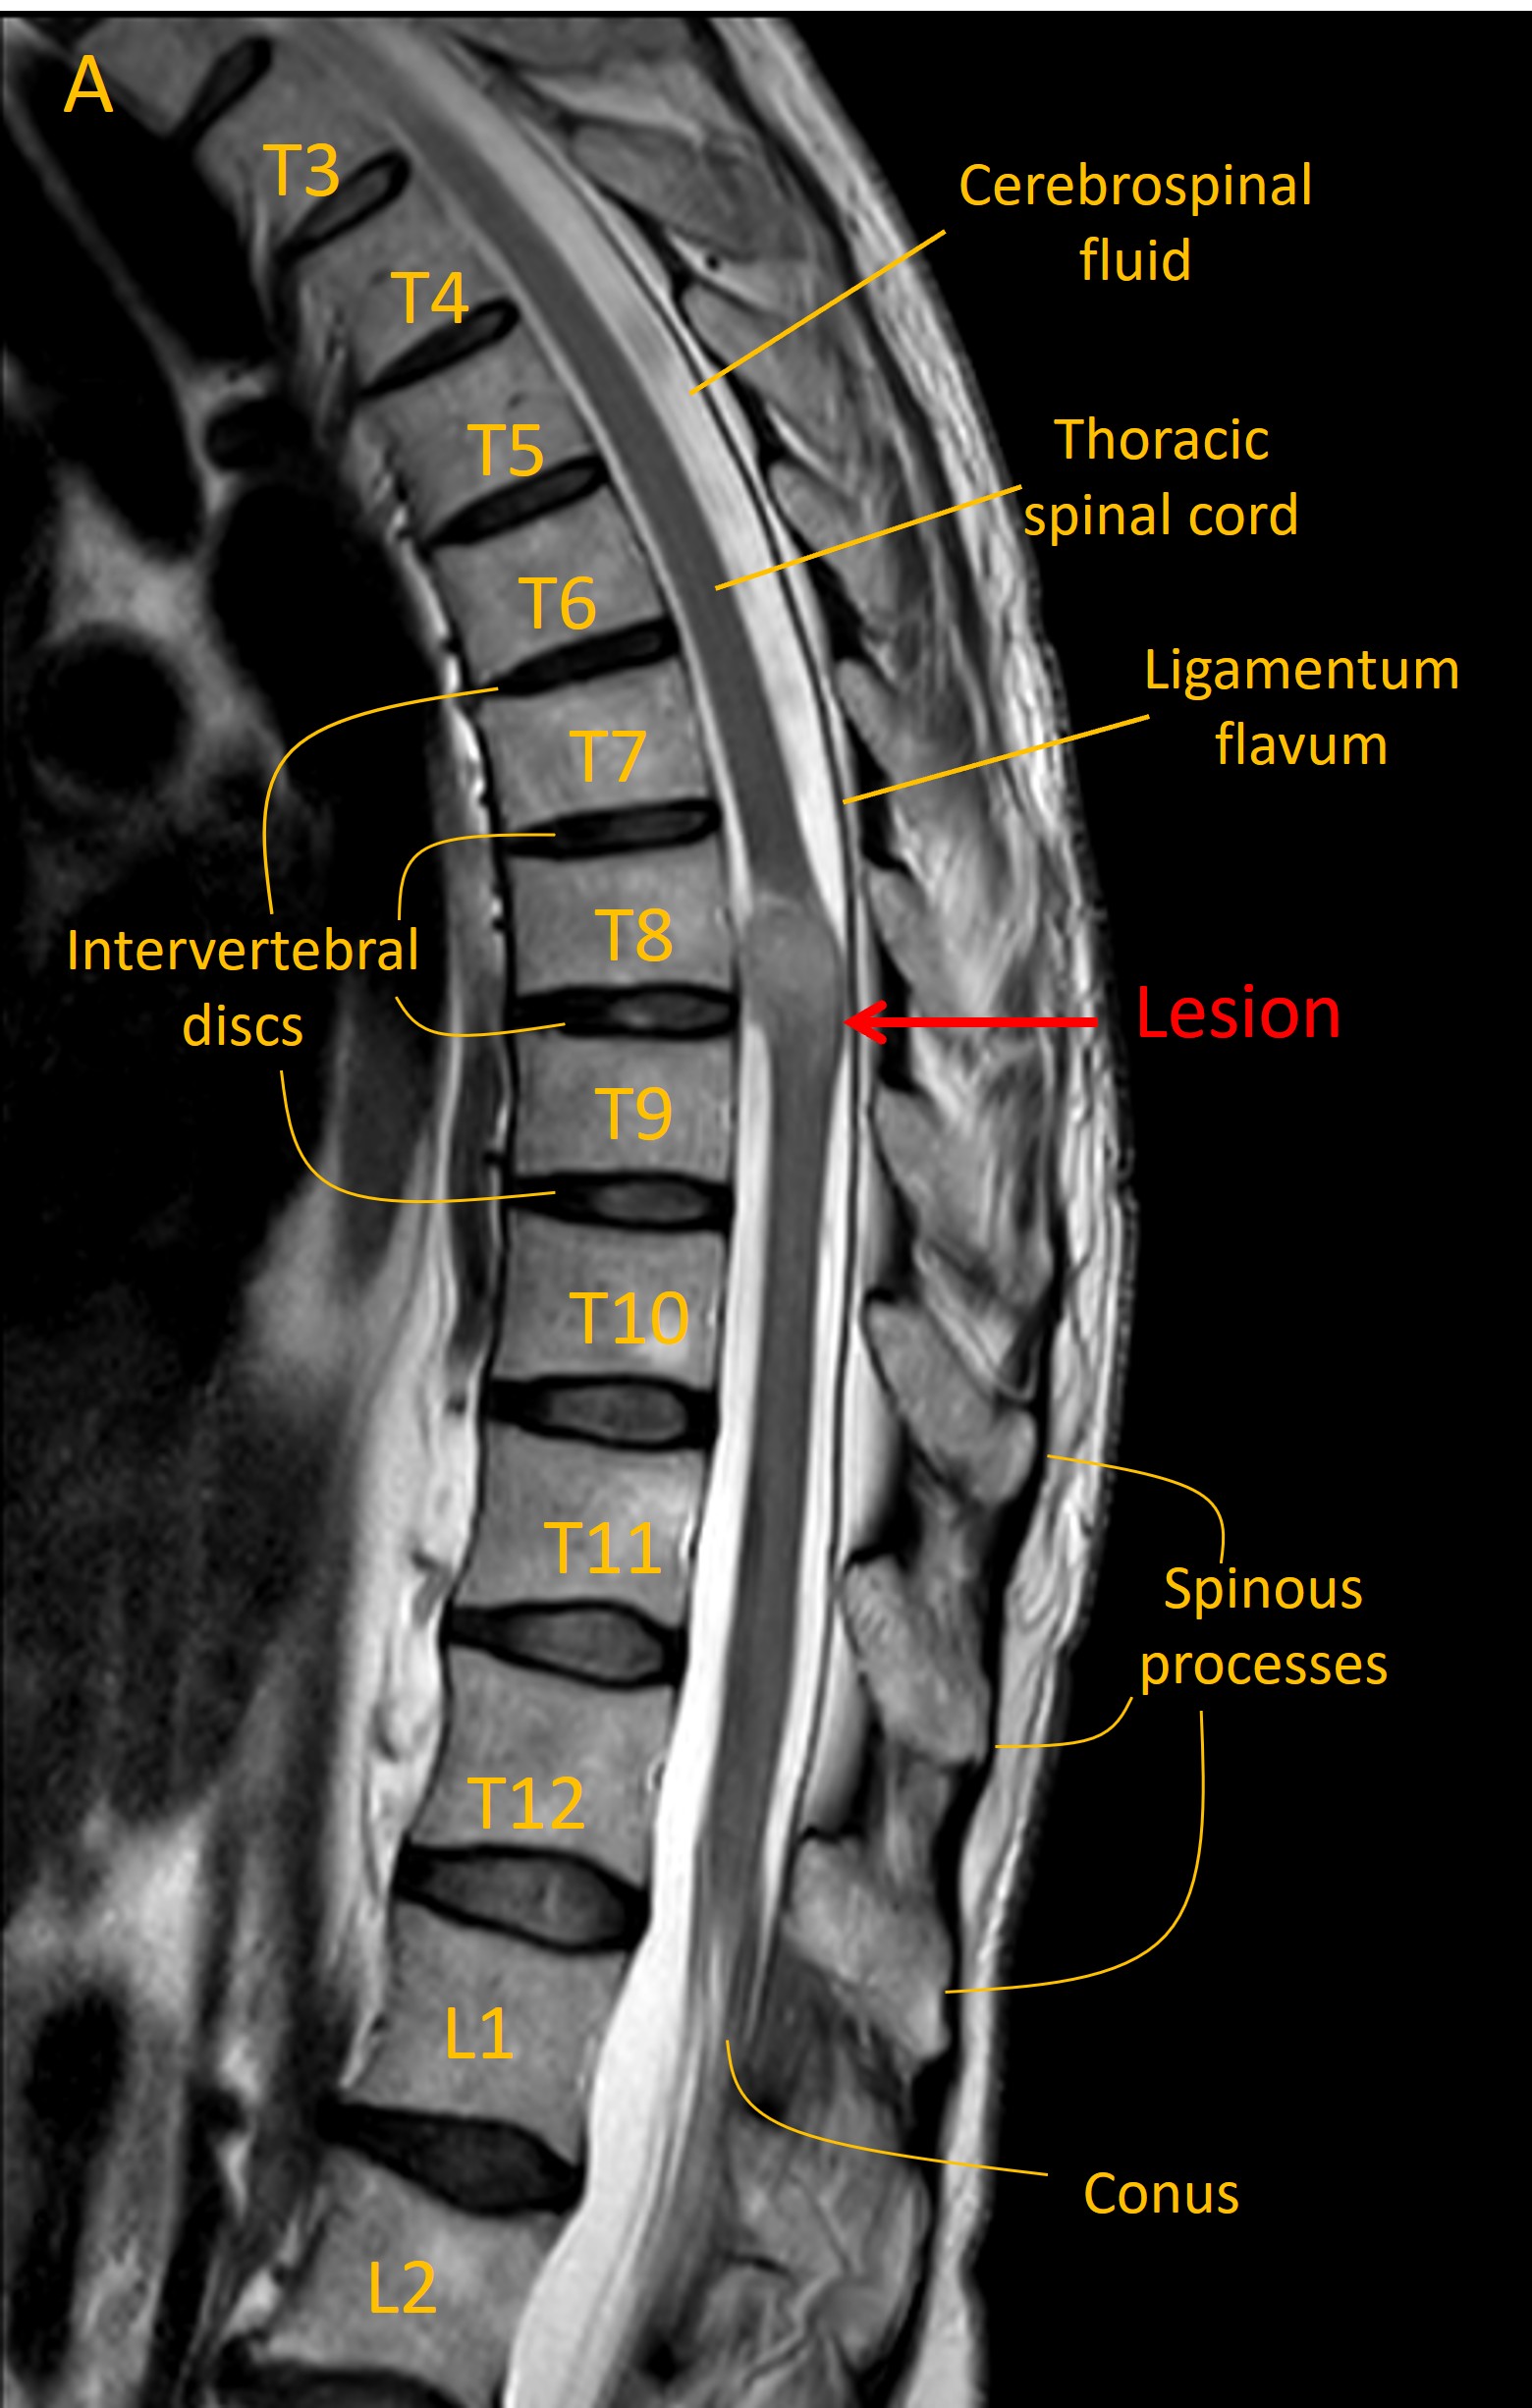

An MRI identified a lesion at T8/9 growing from the meningeal space (Image A, sagittal T2 MRI). This had homogenous contrast enhancement (B, T1 MRI with contrast). There was evidence of lateral displacement of the spinal cord (C, axial MRI).

Contrast T1

Imaging was consistent with a meningioma. Reassuringly there was no evidence of metastatic disease on body imaging.